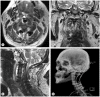

Anterior exposure for cervical chordomas remains challenging because of the anatomical complexities and the restoration of the dimensional balance of the atlanto-axial region. In this report, we describe and analyze the transmandibular transoral approach and multilevel spinal reconstruction for upper cervical chordomas. We report two cases of cervical chordomas (C2 and C2-C4) that were treated by marginal en bloc resection with a transmandibular approach and anterior-posterior multilevel spinal reconstruction/fixation. Both patients showed clinical improvement. Postoperative imaging was negative for any residual tumor and revealed adequate reconstruction and stabilization. Marginal resection requires more extensive exposure to allow the surgeon access to the entire pathology, as an inadequate tumor margin is the main factor that negatively affects the prognosis. Anterior and posterior reconstruction provides a rigid reconstruction that protects the medulla and decreases axial pain by properly stabilizing the cervical spine.